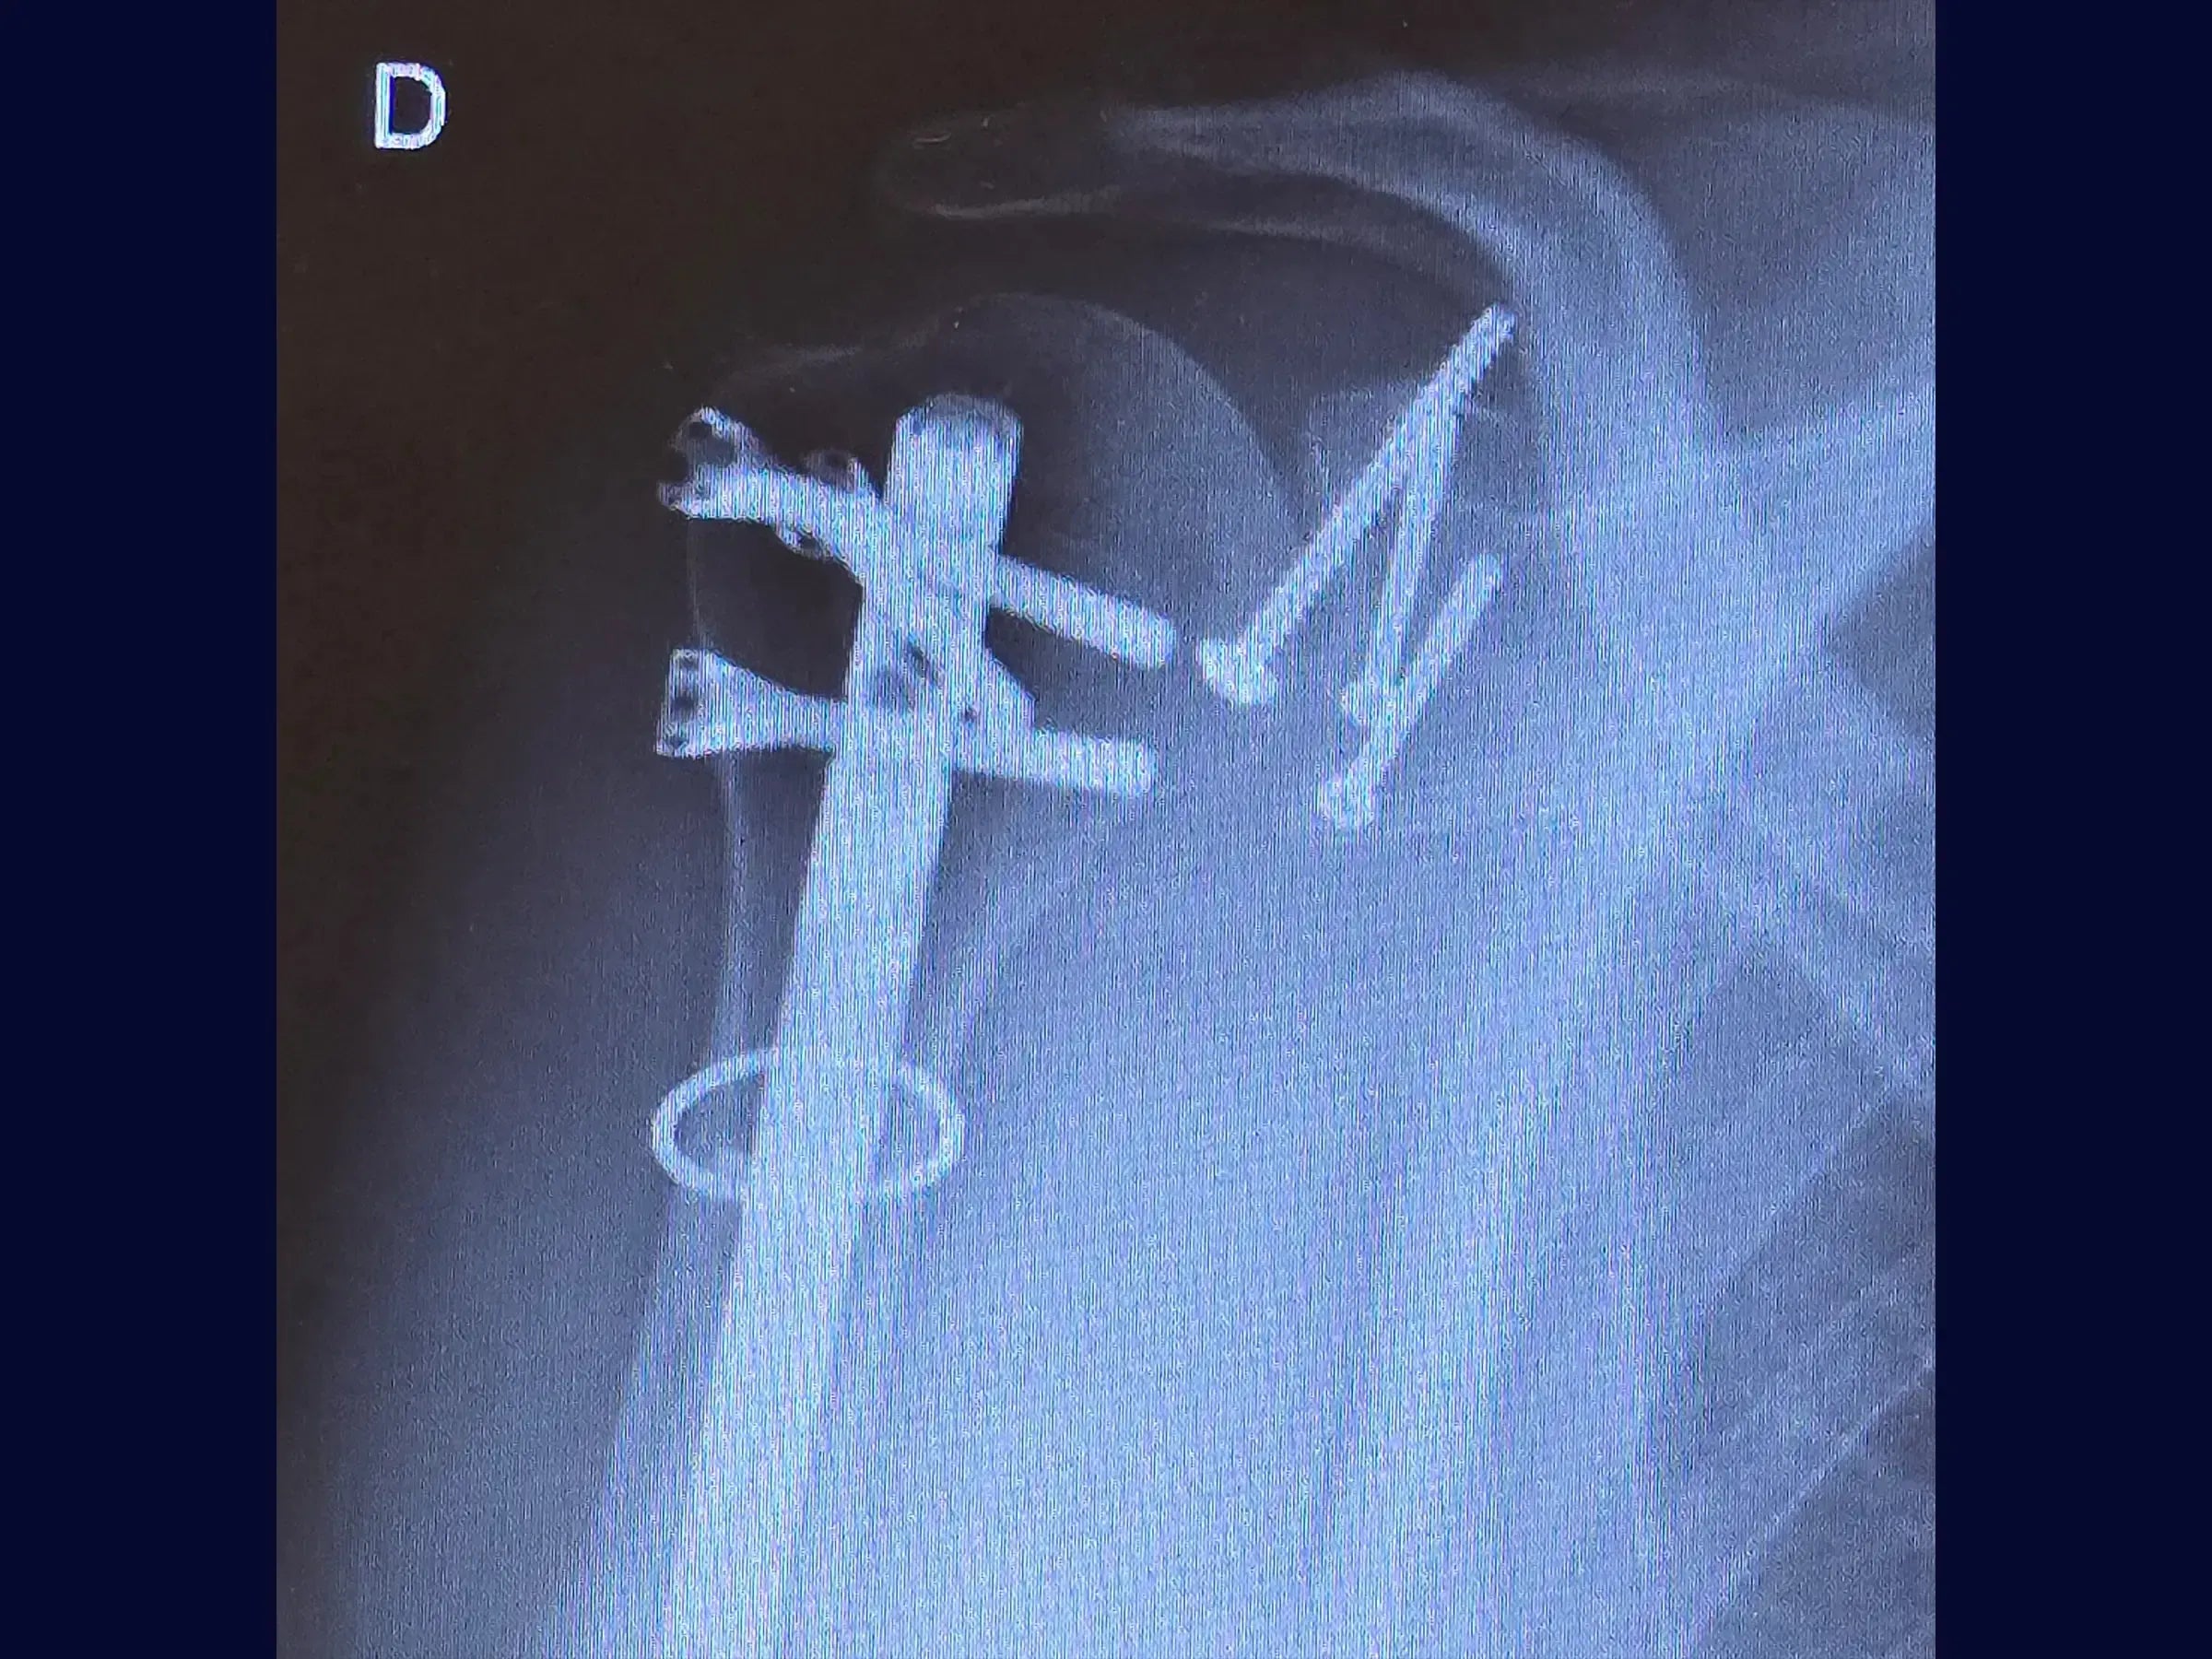

- Osteosíntesis de fracturas glenoideas con tornillos de compresión.

- Osteosíntesis efectiva: demostración de visualización transversal del fragmento y técnica de fijación con tornillos de compresión para la estabilidad de la fractura glenoidea.